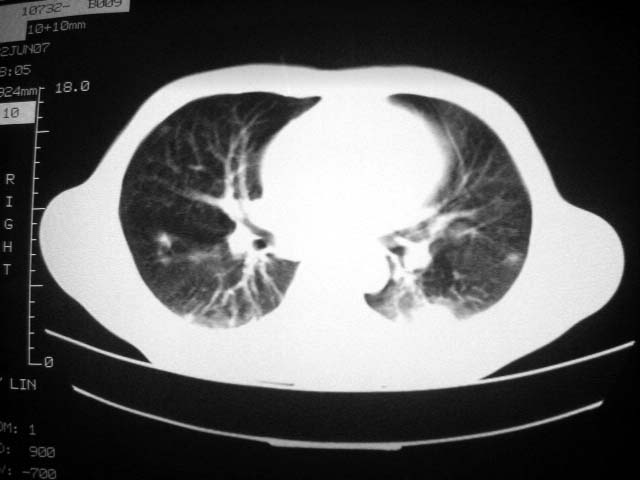

标题: CT7988D:近期图像 出乎意料!

从ct7988c 至今未用任何抗生素及抗痨药,维持保肝治疗。患者低热、咳血渐消失。

07年6月22号复查

前几次大家认为是转移癌,但此次复查病灶却明显吸收好转,不支持诊断。请大家讨论。[emb10]